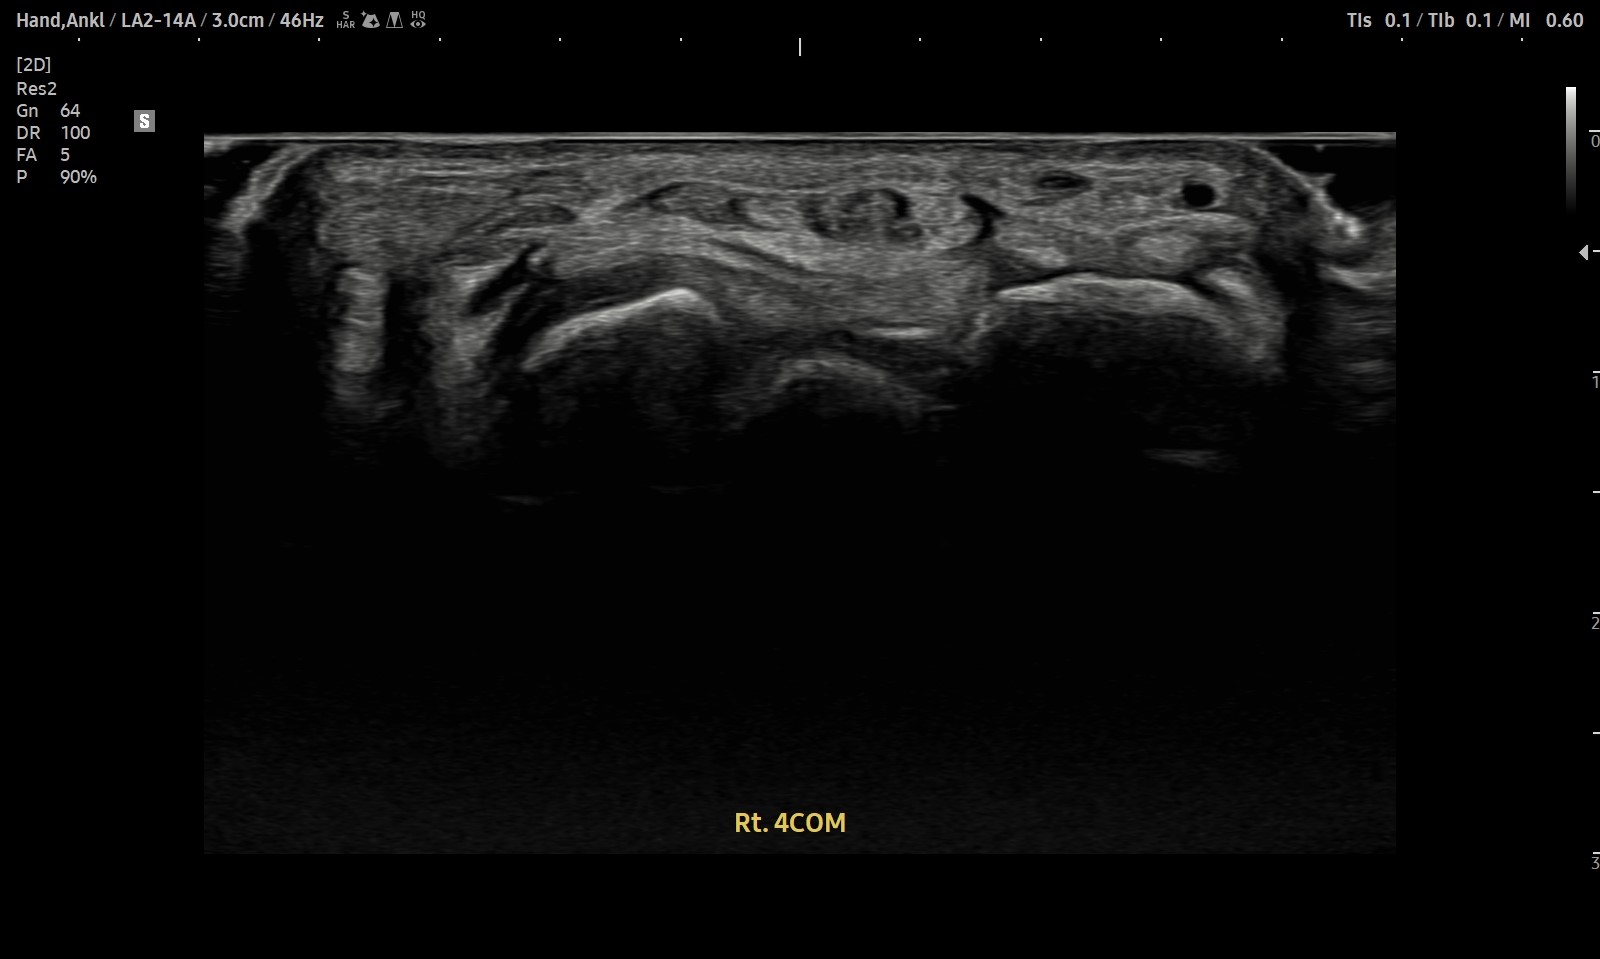

- 치료기간 : 2025 . 6 . 14 ~ 2025 . 7 . 25

- 치료횟수 : 10 회(2cycle)

치료 전

치료 후